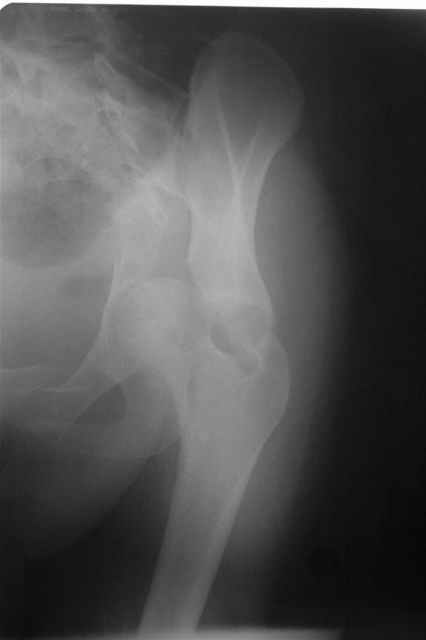

Трудности возникли сразу после рассечения большой ягодичной мыцы - короткие наружные ротаторы едва ли определялись - головка и шейка (как видно на

снимке) ушли в таз, пришлось воспользоваться дистрактором( ручные попытки выдернуть голову из под проксимального фрагмента - безуспешны) Шарнирный дистрактор - великое изобретение, без него репозиция была просто невозможна.

> Трудности возникли сразу после рассечения большой ягодичной мыцы - короткие

> наружные ротаторы едва ли определялись - головка и шейка

> ( как видно на

> снимке) ушли в таз, пришлось воспользоваться дистрактором

P.S. в приложении R пациентки с похожей проблемой доступа.. за исключением того, что перелом

двухколонный. Вертлугу лечили Y доступом.